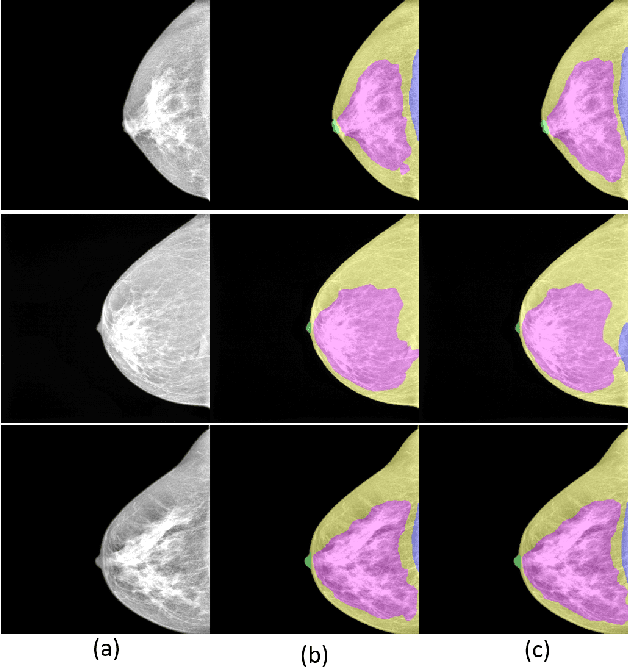

Abstract:Mammography images are widely used to detect non-palpable breast lesions or nodules, preventing cancer and providing the opportunity to plan interventions when necessary. The identification of some structures of interest is essential to make a diagnosis and evaluate image adequacy. Thus, computer-aided detection systems can be helpful in assisting medical interpretation by automatically segmenting these landmark structures. In this paper, we propose a deep learning-based framework for the segmentation of the nipple, the pectoral muscle, the fibroglandular tissue, and the fatty tissue on standard-view mammography images. We introduce a large private segmentation dataset and extensive experiments considering different deep-learning model architectures. Our experiments demonstrate accurate segmentation performance on variate and challenging cases, showing that this framework can be integrated into clinical practice.